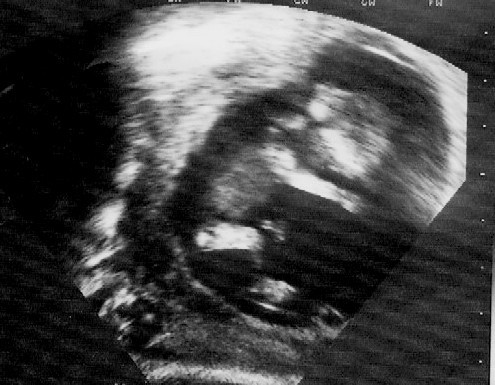

to wlasciwie nie pierwsze zdjecie ale najladniejsze z dotychczasowych :-)

bylo zrobione 19 pazdziernika w 11 tyg i 6 dniu.fasolka miala 52.3mm :-)

chciałam pochwalić się swoim maluszkiem, zdjęcie usg było robione w 12stym tygodniu, teraz jest 15sty. maluch bardzo energicznie baraszkował podczas badania, ale zdjecie wyszło śłiczne i super wyraźne :)